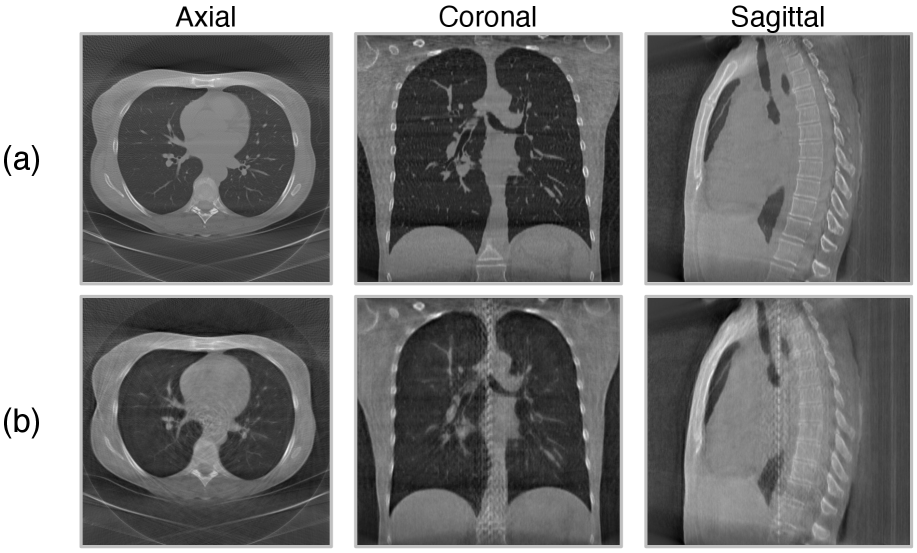

Figure 6: Reconstructed CT volumes in three views. (a) and (b) show reconstruction results with ground-truth projections and rendered projections, respectively. Our method preserves the overall shape and a reasonable degree of low-level structural information. We observe a certain level of blurriness probably due to the abstraction of visual representation learning.

In line with our objective of volumetric knowledge distillation from CT, we conducted experiments to verify whether the learned representations capture 3D information. We trained a VQ-GAN decoder [esser2021taming] on top of the frozen encoder fθf_{\theta} and view predictor gvg_{v}. We trained the decoder with ground-truth projections. At inference time, we utilized the FDK algorithm in the ASTRA toolbox [van2016fast] to reconstruct 3D CT volume from rendered projections. More details are described in the appendix. To optimize projection rendering performance, we varied the codebook size and codebook vector dimension following [sun2024autoregressive]. The trained decoder attained a high codebook usage of 81.6%, which is calculated as the percentage of used codes at inference time. The rendered 2D projections achieved a peak signal-to-noise ratio (PSNR) of 30.23 dB and structural similarity index measure (SSIM) of 0.888. The reconstructed 3D volumes achieved a PSNR of 27.87 dB and SSIM of 0.789. Fig. 6 demonstrates that the reconstructed volume preserves the overall structure and a reasonable level of local details while a certain level of loss in local details occur due to the abstraction of visual representations.